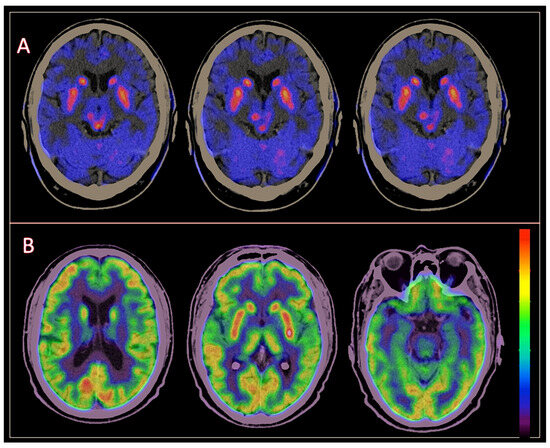

3.2. Brain [18F]DOPA PET/CT Findings

3.3. Brain [18F] FDG PET/CT Findings